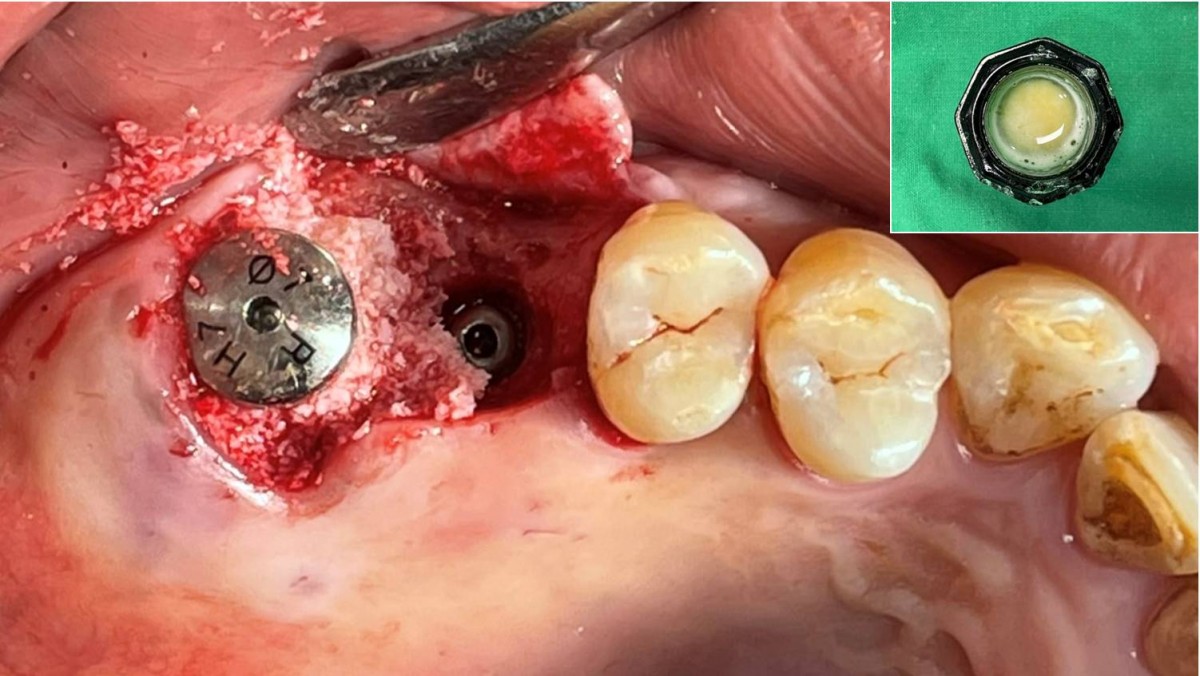

Maxillary Sinus Graft, 2 Implants, Crown Contouring

<GCaks> A 56-year-old male patient had pain-inducing caries, and perio-involved tooth mobility resulted in a tooth fracture at 1st molar. And it was removed months ago. He was a heavy smoker and showed poor oral hygiene.